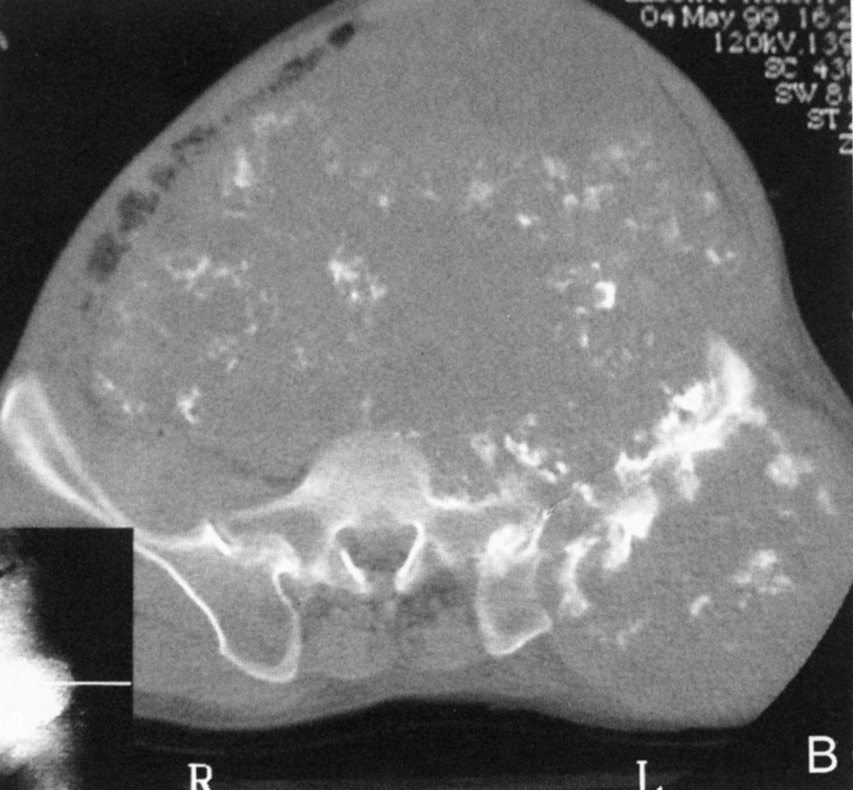

肿瘤内液 - 液平面

肿瘤内液-液平面多数是病灶内囊变出血所致,MRI T2W1 为上部呈高信号下部呈中低信号的液-液平面。CT 可为上部低密度下部高密度的液-液平面(图 32)。液-液平面常见于动脉瘤样骨囊肿、但也可见于骨内腱鞘囊肿(图 33)、囊性血管瘤病等其他肿瘤和肿瘤样病变。

图 32.肿瘤内液-液平面:动脉瘤样骨囊肿